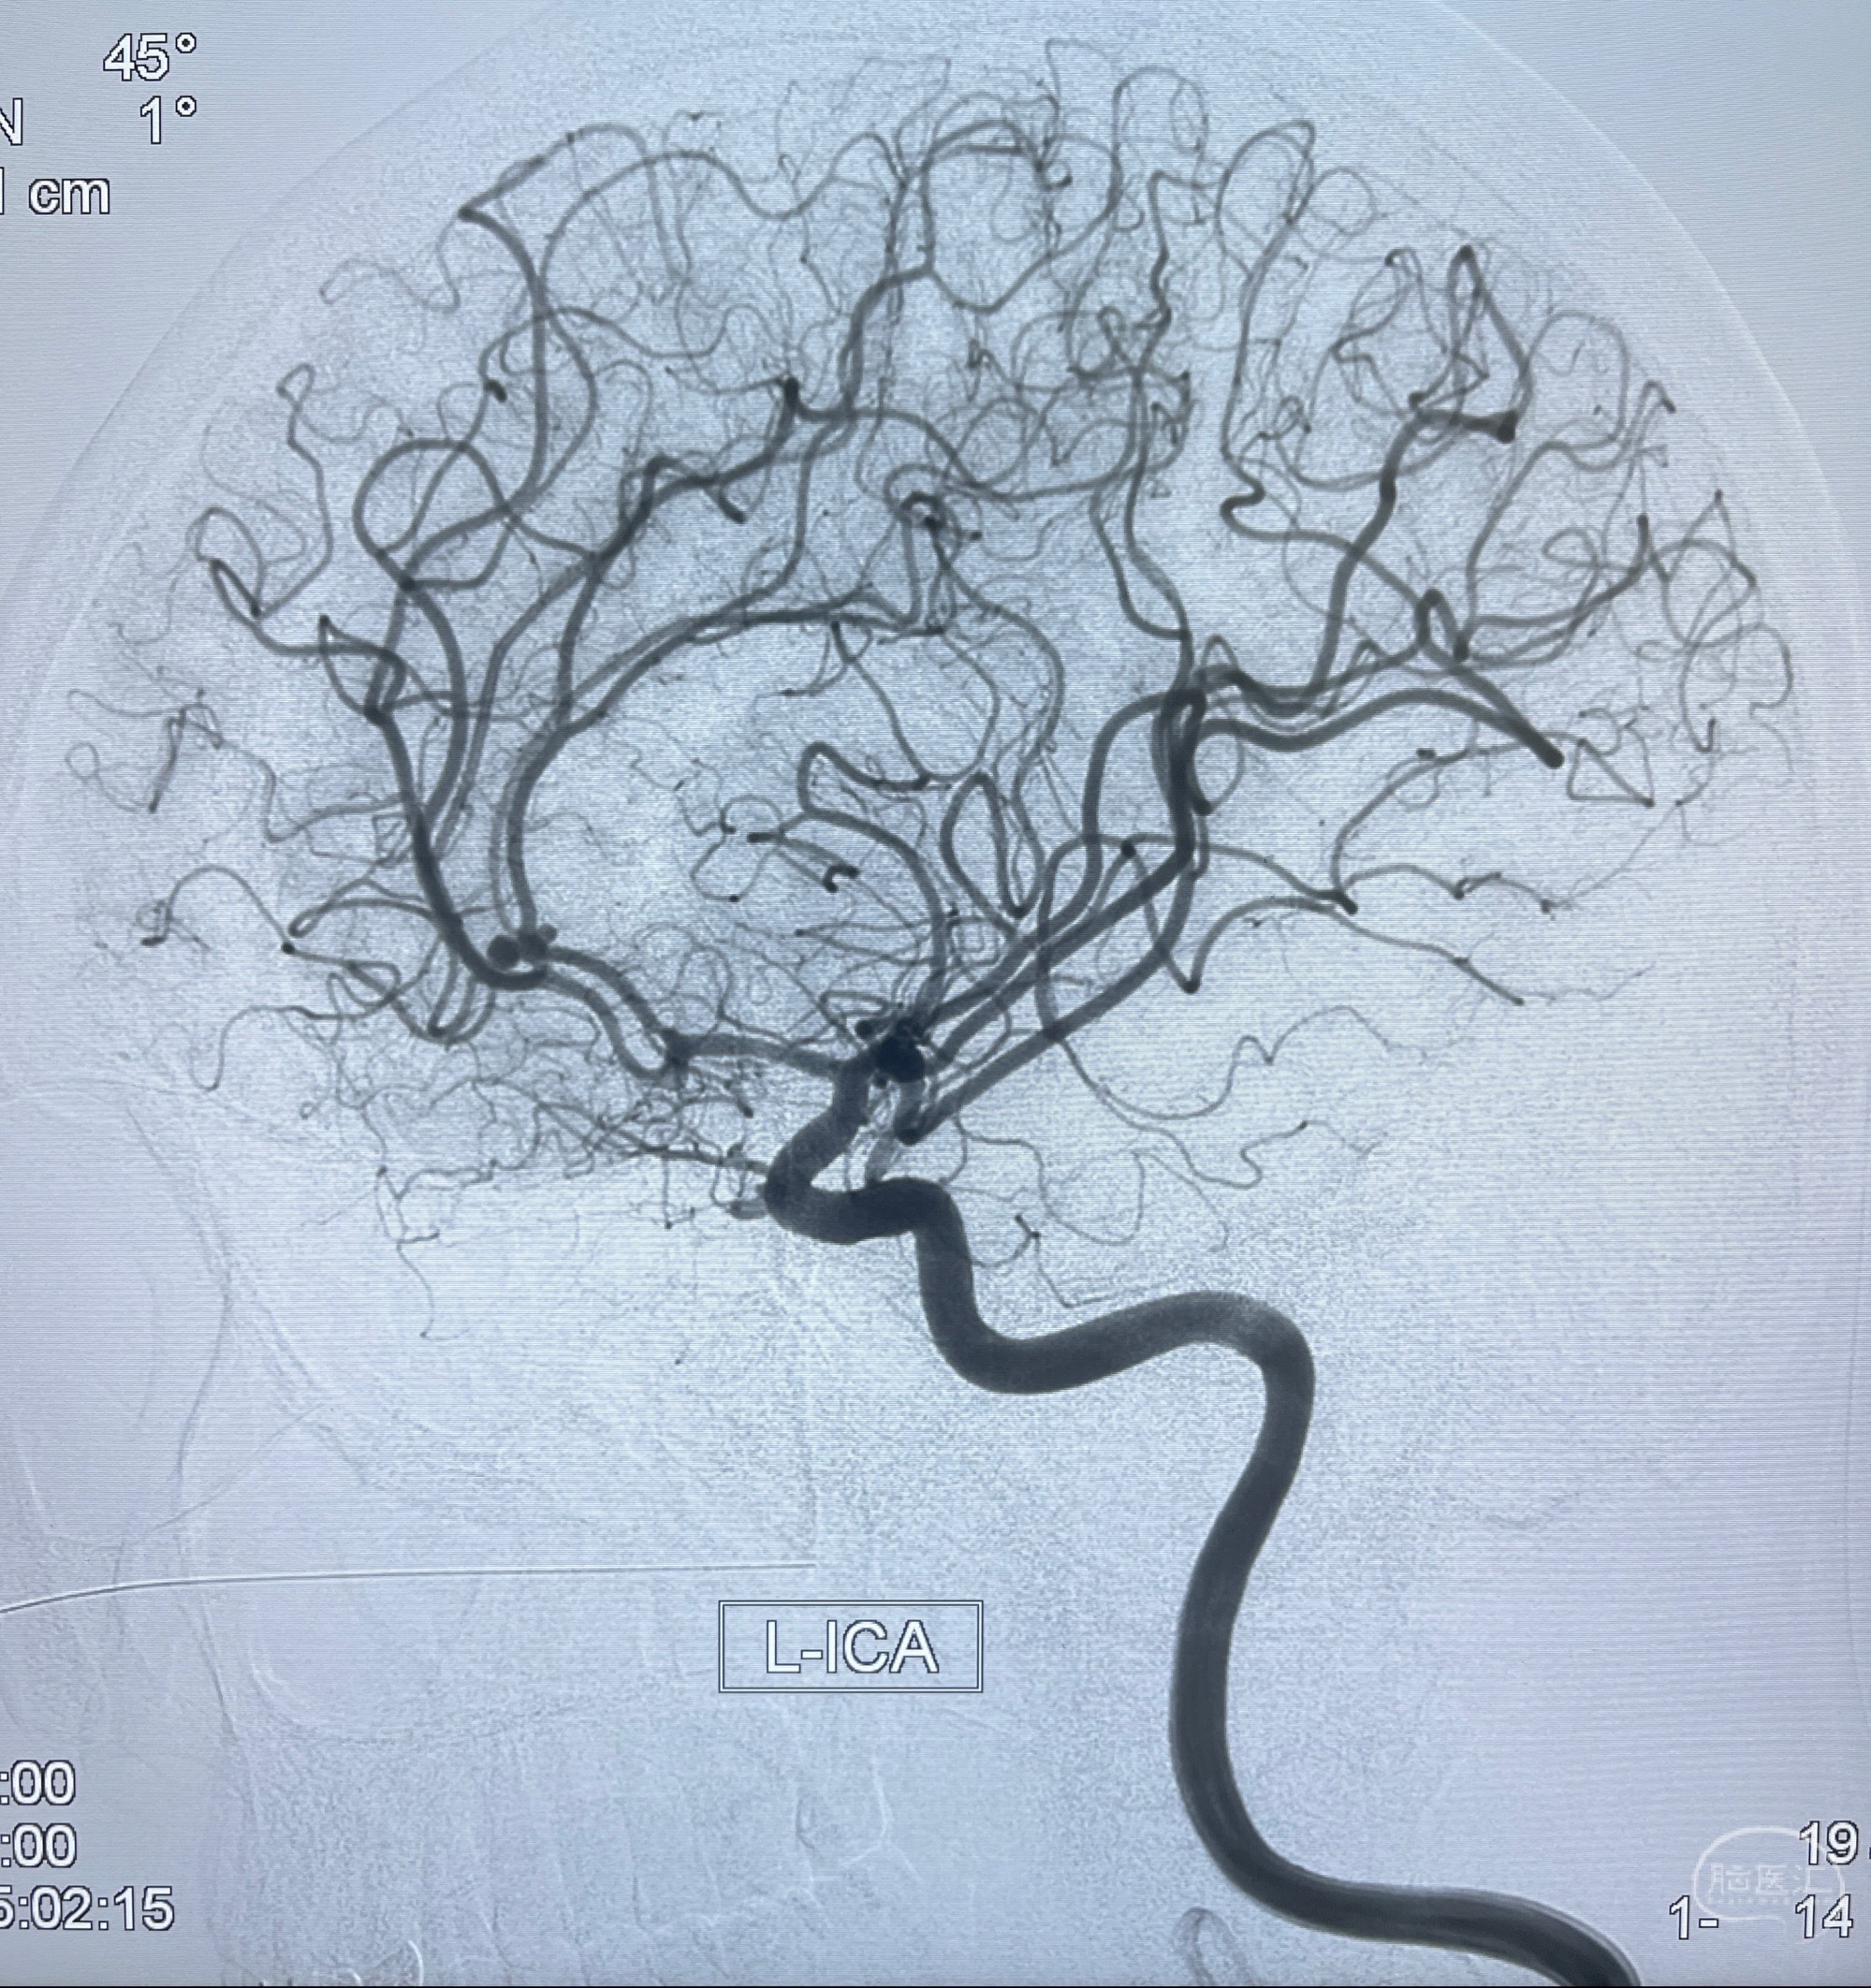

2023-08-23DSA:左侧前交通动脉瘤,左侧A3/4交界处多发动脉瘤